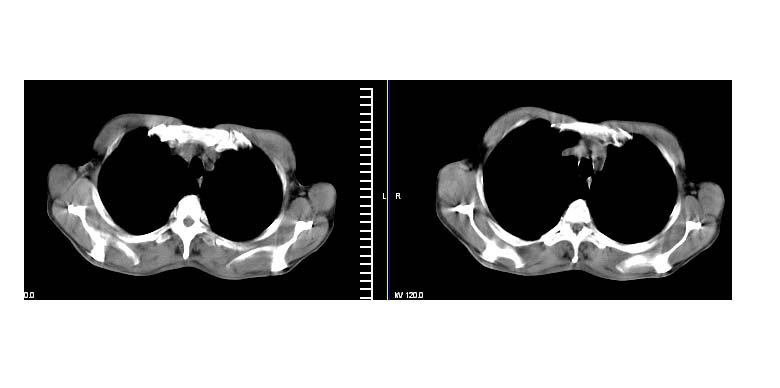

标题: CT11019:男性,66岁。发烧5-6天。治疗后无明显好转。 [打印本页]

标题: CT11019:男性,66岁。发烧5-6天。治疗后无明显好转。

左侧胸廓偏小,左下梭形高密度影,考虑阻塞性肺炎.

斜肋积液

右下肺中央型肺癌伴阻塞性肺炎及肺不张可能性大,建议临床进一步检查(ct增强或纤支镜)

斜裂积液,炎症

明明是斜裂胸膜积液,为何都考虑阻塞性肺炎、肺不张(边缘内凹,而本例是外凸)。